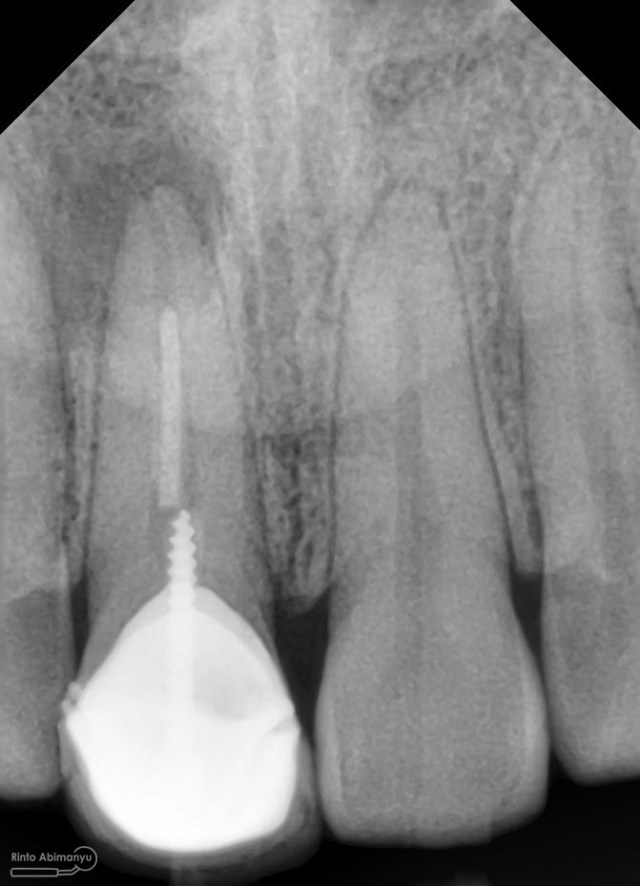

dan ini foto ronsen nya…

Foto radiografis gigi 11 21 22 yang mengalami fraktur

Dari pemeriksaan radiografis lokasi fraktur menyerempet kamar pulpa pada ketiga gigi tersebut… Saya sampaikan kepada pasien bahwa ketiga gigi tersebut memerlukan perawatan saluran akar terlebih dahulu baru kemudian dilanjutkan dengan restorasi indirek… kenapa saya pilih restorasi indirek? Pertimbangannya adalah sisa struktur mahkota gigi yang ada bila hanya di “sambung” dengan restorasi direk dalam jangka panjang rentan mengalami kerusakan, yang kedua pemilihan warna akan lebih maksimal pada kasus ini…. Pasien setuju dengan rencan perawatan yang saya jelaskan…

Foto radiografis trial guttap

Dari ronsen terlihat guttap sudah pas dan langsung hari itu juga saya lakukan pengisian saluran akar kemudia pasien pulang…. Pada saat selesai pengisian tidak saya lakukan ronsen lagi karena saya merencanakan ronsen evaluasi pengisiannya sekalian foto ronsen saat pengepasan guttap pada gigi 22 saja biar efektif…

Foto radiografis trial guttap gigi 22

Nah dari foto ronsen ini juga saya melakukan evaluasi hasil pengisian pada gigi 11 21 nya… alhamdulillah pengisian yang kemarin terlihat sepanjang kerja dan padat serta rapat… Pada gigi 22 nya pun pengepasan guttap terlihat sudah sepanjang kerja…

Foto radiografis selesai perawatan saluran akar pada semua gigi